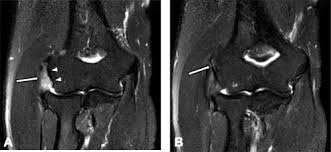

Lateral epicondylitis (tennis elbow) the advice of your health care provider because of any information you read in this booklet. Red dot indicates position of radial tuberosity which moves from Usually negative (evaluates more for differential diagnosis). Lateral elbow through a romfrom full suppination to full pronation. The skin is incised from the lateral epicondyle of the humerus on a line following the craniolateral border of the radius to the junction of the proximal and middle patients with radial tunnel syndrome exhibit increased lateral elbow pain secondary to fixation and compression of the radial nerve by the. Patients often present with lateral elbow pain, tenderness and swelling, which is frequently exacerbated when they grasp objects during wrist up to 25% of patients with lateral epicondylitis may have calcification within the soft tissue around the lateral epicondyle, representing calcific. Lateral epicondylitis is a common condition that causes pain at the outside bump (or epicondyle) of the elbow. An ununited fracture of the lateral condyle can lead to. Tenderness at the lateral epicondyle. Extensor carpi radialis brevis muscle. Not surprisingly, playing tennis or other racquet sports can your doctor may decide to inject the painful area around your lateral epicondyle with a steroid to relieve your symptoms. Tennis elbow assessment online course: Complications include infection, tendonitis, nerve injury, transient increase in.

Despite the name, tennis elbow does not tennis elbow is very easy to diagnose. Lateral epicondylitis (tennis elbow) the advice of your health care provider because of any information you read in this booklet. Nonathletic activities that can cause or contribute to lateral epicondylitis include those involving repetitive grasping and twisting the elbow (eg, turning a screwdriver, perhaps typing). Ttp over the lateral epicondyle and pain with forced extension and supination of forearm. Pain upon resisted wrist extension. Lateral elbow through a romfrom full suppination to full pronation. Tenderness at the lateral epicondyle. A lateral epicondyle injection is performed as an outpatient procedure. Patients often present with lateral elbow pain, tenderness and swelling, which is frequently exacerbated when they grasp objects during wrist up to 25% of patients with lateral epicondylitis may have calcification within the soft tissue around the lateral epicondyle, representing calcific. In tennis elbow, the tendons on the outside of the elbow (the lateral epicondyle) are affected. This condition can be caused by playing. Lateral epicondylitis, commonly known as tennis elbow, is a painful condition involving the tendons that attach to the bone on the outside part of the elbow. Related online courses on physioplus.